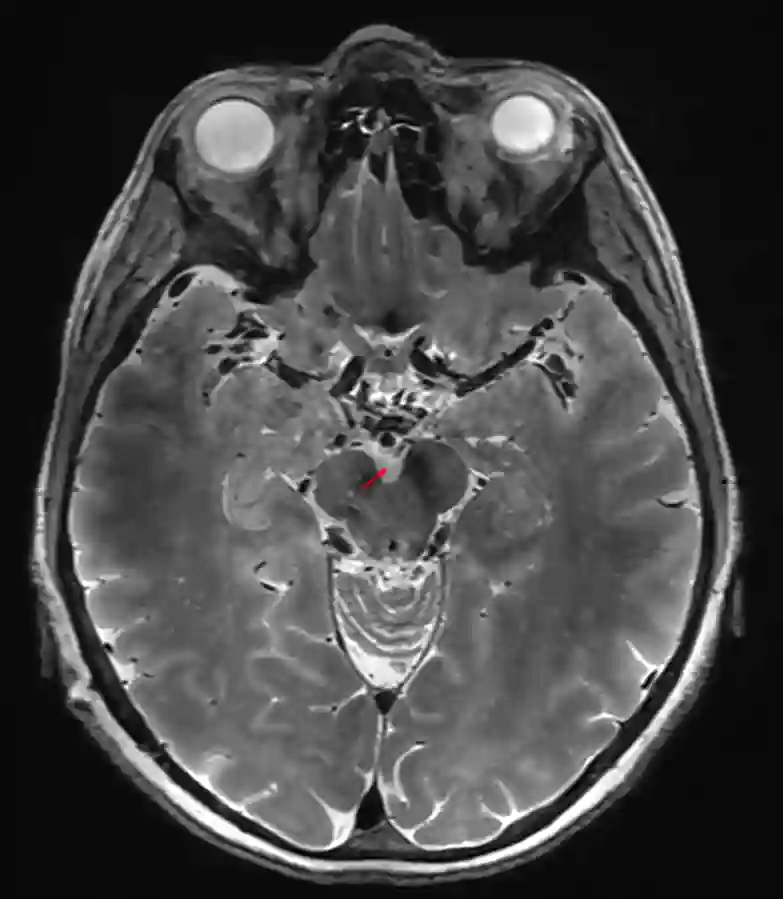

Cisterna interpeduncularis

Darstellung der Cisterna interpeduncularis (roter Pfeil) in einer axialen T2 MRI Sequenz.